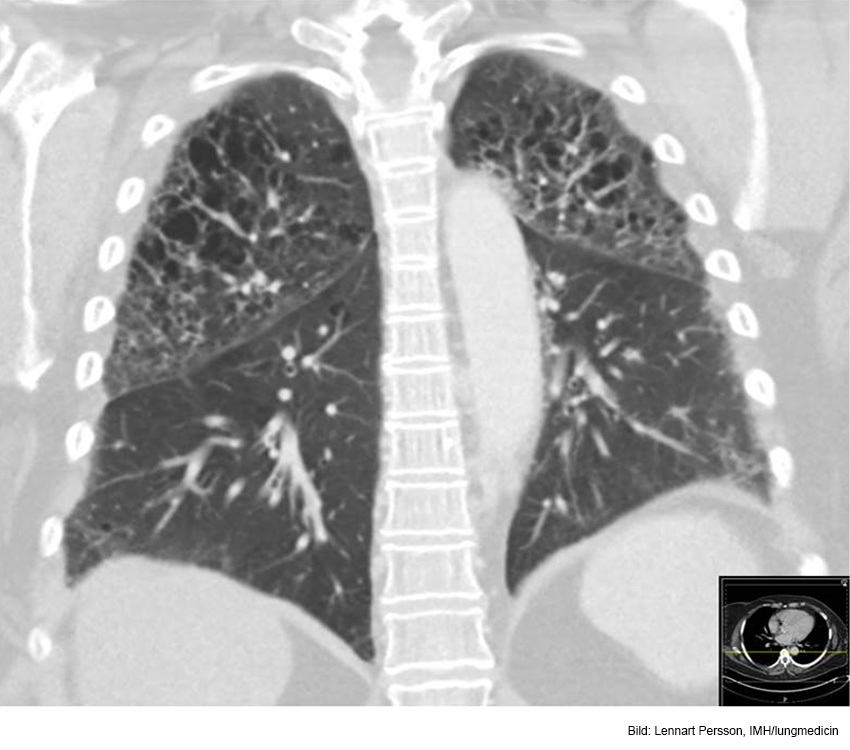

Vad visar röntgen?

A

Bild förenlig med t ex KOL

Gles kärlteckning, särskilt apikalt (emfysem ev) och antytt avplanade diafragmakupoler, särskilt höger, förenligt med KOL. Något förstorat hjärta men ingen stas.

Litet infiltrat basalt höger